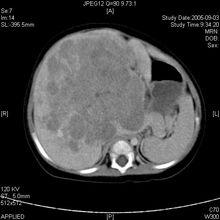

5、腎囊腫(多囊腎)

4.代謝異常及先天性疾病:如腎結石,糖尿病性腎病,澱粉樣變,腎小管酸中毒,遺傳性腎炎,多囊腎,范可尼綜合徵。